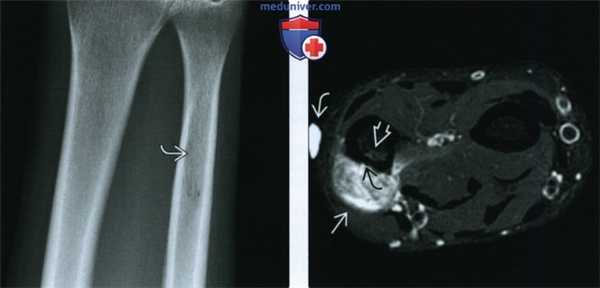

(Слева) Рентгенография в ПЗ проекции: у мужчины 31 года с болью в дистальном отделе предплечья визуализируется только неясный участок просветления, указывающий на наличие патологического очага в дистальном отделе локтевой кости.

(Справа) МРТ, аксиальная проекция, режим Т2 с подавлением сигнала от жира: крупное неоднородное мягкотканное образование, явившееся причиной неровности кортикального слоя. Визуализируется зона гиперинтенсивного сигнала в структуре костного мозга, что позволяет предполагать интрамедуллярное распространение процесса. Наружная метка указывает на область болезненности. Поверхностный очаг с фестончатостью кортикального слоя является типичным для периостальной ОС.

(Слева) МРТ в аксиальной проекции, с подавлением сигнала от жира, с контрастным усилением: Контрастное вещество накапливается патологическим очагом вокруг зоны некроза. Наиболее важно контрастное усиление подозрительного участка костного мозга. Этим подтверждается факт поражения костномозгового канала, что требует выполнения широкой резекции. К сожалению пациенту была выполнена только краевая резекция мягкотканного компонента опухоли.

(Справа) МРТ, аксиальная проекция, режим Т2 с подавлением сигнала от жира, через шесть месяцев после краевой резекции: рецидив опухоли с поражением как мягких тканей, так и костномозгового канала.